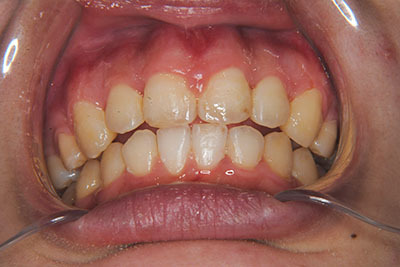

おとなの方でも矯正治療をあきらめないでください!

矯正歯科治療は子供の頃だけしかできない……

子供の頃に比べ大人になったら治療期間がすごく長い……

というようなイメージをお持ちではありませんか?

子供の頃に矯正治療を行う方が治療期間が短く済むというのは、確かですが、矯正治療は患者様の意識も重要です。

いくら歯が動き易くとも、本人がやる気でなければ効果は出ませんし、むし歯発生のリスクも高まります。おとなの方は顎の成長が終わっているため、治療の計画が立てやすいとも言えます。「もう大人だから…」とあきらめず、一度ご相談ください。